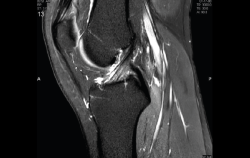

Resonancia magnética

Se basa en la propiedad que poseen los núcleos de hidrógeno de absorber energía electromagnética cuando están sometidos a un campo magnético intenso. La RM representa un mapa de la densidad de protones, o sea, de la distribución de agua por el organismo(12).

Se consiguen unas imágenes de alta resolución para la valoración de meniscos, ligamentos y tendones. Además, es especialmente útil en las rodillas operadas, lesiones tumorales, evaluación del cartílago y la visualización de los nervios(13).

1. Estudio de las estructuras intraarticulares

Es la prueba no invasiva de elección para valorar las lesiones internas de la rodilla(2). Aunque el estudio por RM es a menudo considerado como la prueba diagnóstica de elección para la detección de alteraciones meniscales, se asocia en ocasiones con errores diagnósticos(16).

1.1. Meniscos

Se identifican como estructuras hipointensas en todas las secuencias, con asta anterior y posterior de morfología triangular.

La RM es la técnica de elección en el diagnóstico de la patología meniscal(17)(Figuras 30, 31, 32, 33, 34 y 35).